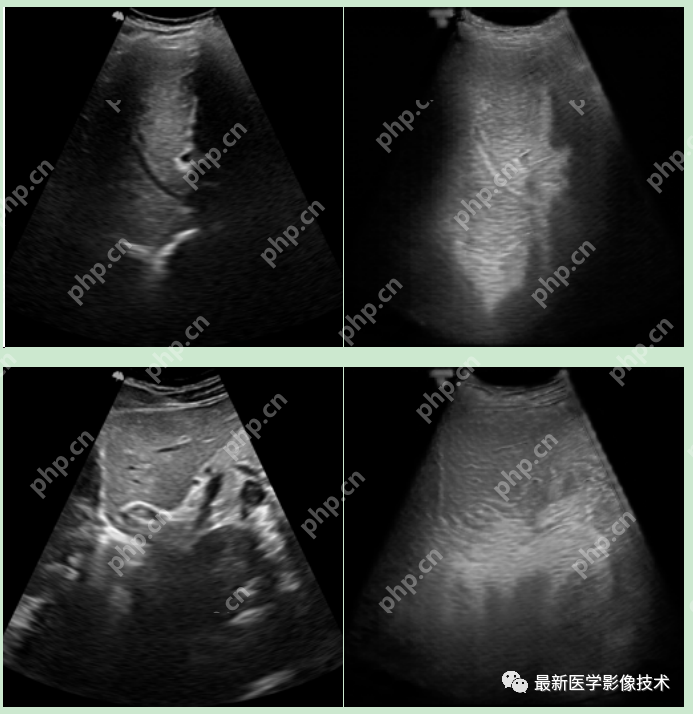

6、测试集部分生成结果

左图为低质量图像,右图为生成的高质量图像。